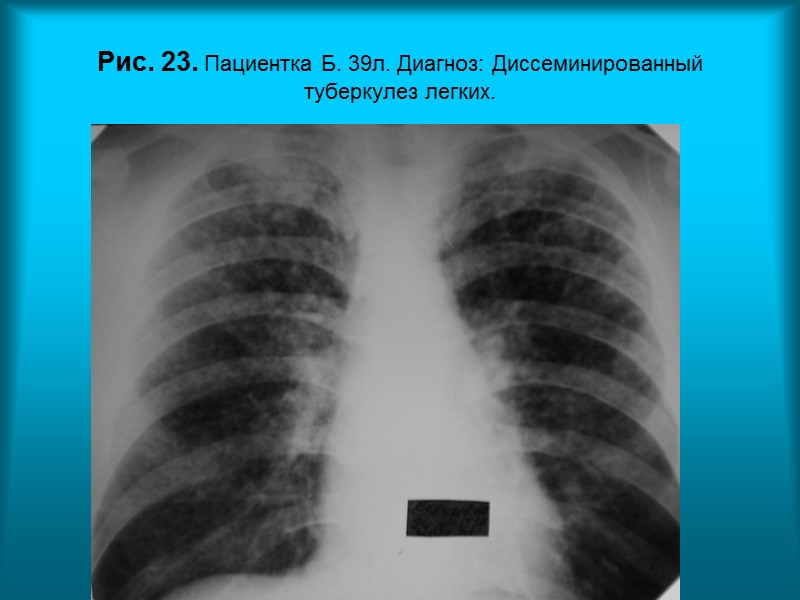

Н.С. Воротынцева. С.С. Гольев Рентгенопульмонология Рис. 23. Пациентка Б. 39л. Диагноз: Диссеминированный туберкулез легких.